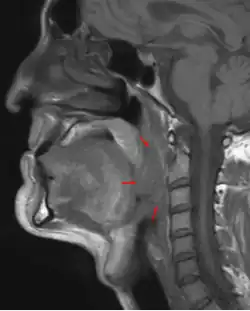

Oropharyngeal cancer (from right tonsil, HPV-negative), T4a N2c, 48-year-old man.